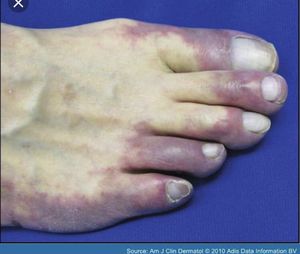

Blue toe syndrome is one of the frequent manifestations of tissue ischaemia. It is caused by the occlusion of small vessels, and usually occurs in elderly men who undergo an invasive vascular procedure.